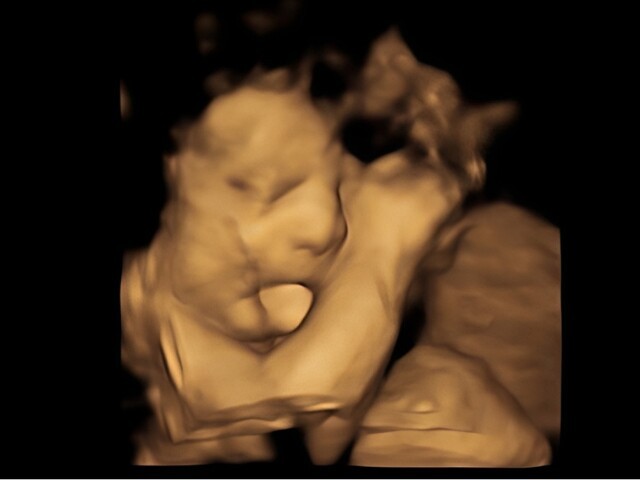

Hình ảnh trên màn hình hiện lên một thai nhi nhỏ đang cuộn mình trong tử cung, tay chân khẽ cử động. Bất ngờ, em bé thè lưỡi ra, chuyển động nhẹ như đang “tương tác”.

A Trạch xúc động, nắm tay bạn gái thì thầm: “Em nhìn kìa, con thè lưỡi, đáng yêu quá! Hay mình giữ con lại nhé, khó mấy cũng cùng nhau vượt qua”. Lâm Hiểu rưng rưng gật đầu.

Theo kết quả siêu âm, thai nhi không thấy xương mũi - dấu hiệu bất thường nghiêm trọng. Hành động “thè lưỡi” mà hai người cho là đáng yêu thực chất có thể liên quan đến hội chứng Down, với các đặc điểm như khoảng cách mắt rộng, không có xương mũi, lưỡi thường đưa ra ngoài. Ngoài ra, chỉ số phát triển của thai cũng chậm hơn so với tuổi thai.